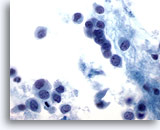

Figure 47

Breast FNA, Lobular carcinoma.

Lobular carcinoma aspirates tend to be sparsely cellular, but occasionally contain many cells as in this example. The tumor cells are single, but may form small aggregates, often with a single file appearance. 20x

Figure 47

Breast FNA, Lobular carcinoma.

Lobular carcinoma aspirates tend to be sparsely cellular, but occasionally contain many cells as in this example. The tumor cells are single, but may form small aggregates, often with a single file appearance.

20x